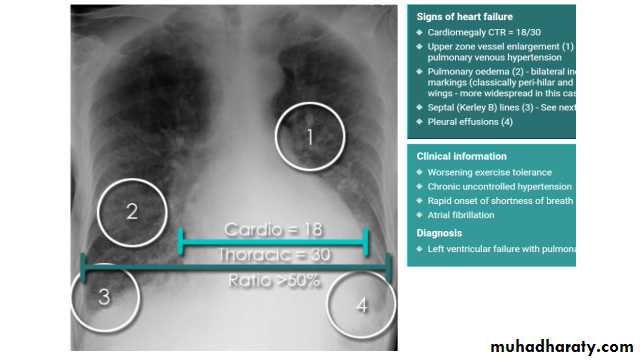

Cardiothoracic ratio (CTR) = Cardiac Width : Thoracic Width

A CTR of greater than 1:2 (50%) is considered abnormal. This however, assumes the projection is Posterior-Anterior (PA), and that cardiac size is not exaggerated by factors such as patient rotation or an incomplete breath in .

The cardiothoracic ratio aids in the detection of cardiomegaly, or more broadly, HYPERLINK "http://radiopaedia.org/articles/enlargement-of-the-cardiac-silhouette" enlargement of the cardiac silhouette.

Congestive cardiac failure (CCF) is a form of cardiac failure which is primarily manifested by the heart inability to pump the volume of blood. It can affect the left (common) or right cardiac chambers or both.

With left sided congestive cardiac failure, the features are that of pulmonary edema which includes:

central pulmonary venous congestion ( prominent hilum )

cephalisation of pulmonary veins ( upper lobe pulmonary venous diversion )

pulmonary interstitial oedema

pulmonary alveolar oedema

Cardiomegaly

Pleural effusion

radiograph include if pressure > 25 mmHg the findings of :

cardiac size/cardio-thoracic ratio: useful for assessing for an underlying cardiogenic cause or associationbat wing pulmonary opacities

presence of HYPERLINK "http://radiopaedia.org/articles/peri-bronchial-cuffing-2" peri-bronchial cuffing

septal lines: HYPERLINK "http://radiopaedia.org/articles/septal-lines-in-lung" Kerley lines become more prominent

pleural effusions

pulmonary venous engorgement/pulmonary blood flow distributionupper lobe pulmonary venous diversion